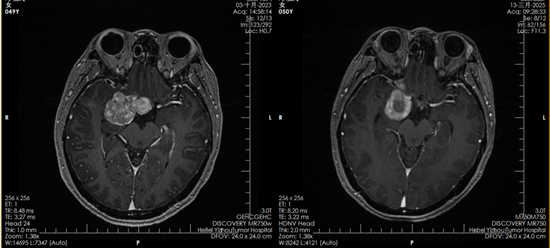

2023年10月,邓女士正式开始质子治疗。一个多月里,她接受了30次治疗。“治疗的时候一点感觉都没有,就像躺下来休息一会儿。要不是看到复查影像里的肿瘤变化,我都不敢相信这是真的。”邓女士说。

质子治疗前后对比影像

从确诊到复发,再到一次次走进手术室,哪怕是被医生告知“没有手术机会”,邓女士始终没有放弃。推车滚轮的声响、病房里辗转难眠的夜晚、治疗带来的痛苦与不安,她都挺了过来。如今,复查影像显示肿瘤已被有效控制,她的坚持终于换来了可喜的结果。